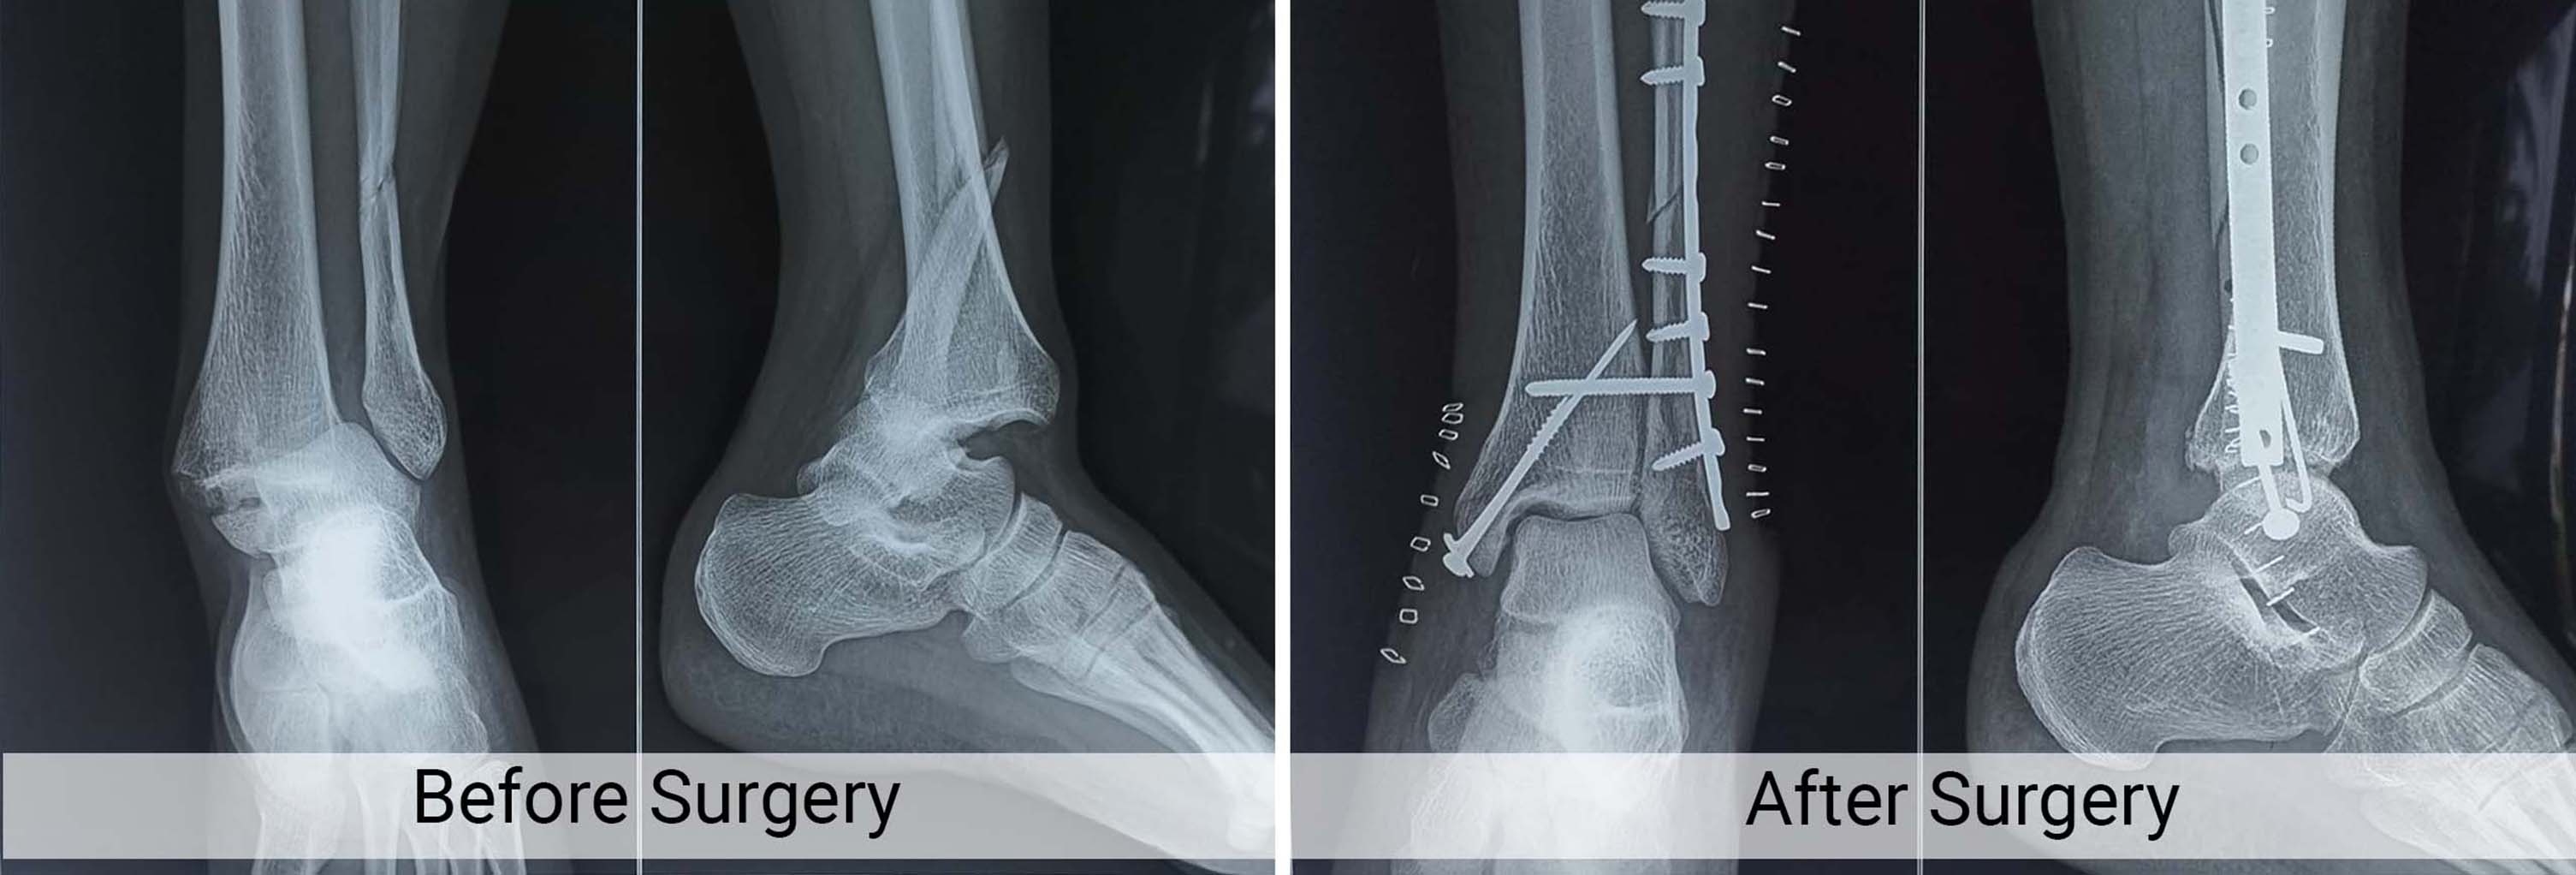

Trauma Fracture